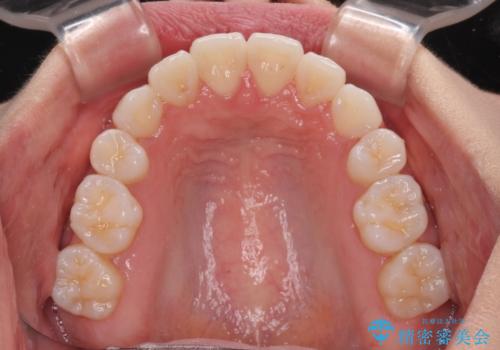

- 八重歯と、それによる正中のズレを気にして来院された患者様です。

口元の突出感は気にしていなかったため、上顎の左右第一小臼歯を抜歯することで、八重歯の解消と上顎の正中を改善していくこととしました。

奥歯の咬み合わせを維持しながら正中位置を改善するために、補助装置を使用しました。

予定より期間がかかりましたが、上下の正中位置を綺麗に一致させることができました。